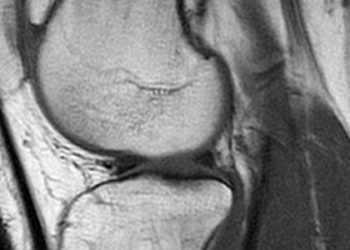

Study Rundown: Meniscal tears are a common knee injury and are often treated with arthroscopic medial meniscectomy. Although it is frequently performed, there is limited evidence from clinical trials to support the efficacy of this procedure. This multicentre, randomized, controlled trial including patients with degenerative medial meniscus tears found no significant difference in outcomes between arthroscopic partial meniscectomy and a sham surgical procedure. This suggests that patients may be undergoing unnecessary treatment and incurring excess cost to the health care system. The strength of this study lies in the design, which included blinding of patients, data collectors, and data analyzers, facilitated by the use of a sham surgery. It has been suggested that patients undergoing arthroscopic partial meniscectomy may be at a higher risk of developing osteoarthritis. Untreated tears are also at risk of developing into osteoarthritis. Prolonged follow-up will be required in order to assess these long-term outcomes.

In-Depth [randomized, controlled study]: This multicentre, double-blind, randomized, controlled trial assigned 146 patients with symptoms of a degenerative medial meniscal tear and without signs of osteoarthritis to undergo athroscopic partial meniscectomy or a sham surgery. The primary outcomes were the changes from baseline to 12 months in the Lysholm knee score, the Western Ontario Meniscal Evaluation Tool (WOMET) score, and knee pain following exercise assessed on a scale from 0 (no pain) to 10 (extreme pain). The Lysholm and WOMET scores both range from 0 to 100, with 0 indicating severe symptoms and 100 indicating no symptoms. Improvements in the three outcome measures were observed in both groups at 12 months; however, no significant between-group differences were observed. The mean between-group difference in improvement in the Lysholm knee score was -1.6 points (95% confidence interval [CI], -7.2 to 4.0), that in the WOMET score was -2.5 points (95% CI, -9.2 to 4.1), and that in knee pain after exercise was -0.1 points (95% CI, -0.9 to 0.7). There was no significant difference between groups in the need for subsequent knee surgery or in the occurrence of serious adverse events.